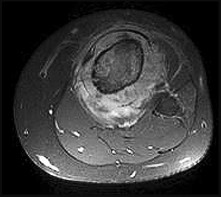

Figures 22a and 22b are the anteroposterior knee radiograph and an axial T2-weighted MR image of an 11-year-old boy who experienced knee pain following soccer practice. What is the best approach for biopsy?

The biopsy should cross only 1 compartment if possible and proceed as directly as possible to the tumor. The lateral parapatellar and medial parapatellar approaches cross the knee joint, potentially visualizing tumor into the knee. A direct anterior approach will contaminate an extensive portion of the quadriceps muscle and potentially complicate limb salvage. Biopsy should be performed at the institution at which definitive resection is planned.